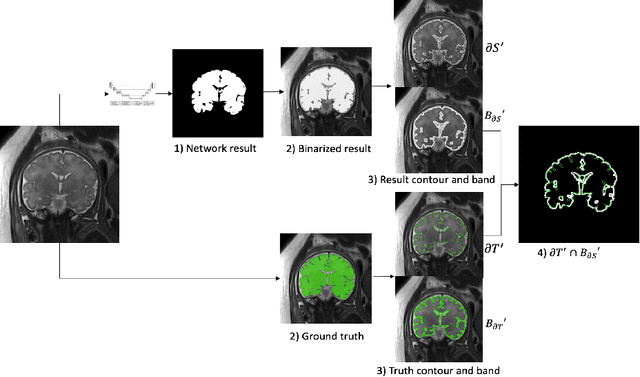

Abstract:Quality control of structures segmentation in volumetric medical images is important for identifying segmentation errors in clinical practice and for facilitating model development. This paper introduces SegQC, a novel framework for segmentation quality estimation and segmentation error detection. SegQC computes an estimate measure of the quality of a segmentation in volumetric scans and in their individual slices and identifies possible segmentation error regions within a slice. The key components include: 1. SegQC-Net, a deep network that inputs a scan and its segmentation mask and outputs segmentation error probabilities for each voxel in the scan; 2. three new segmentation quality metrics, two overlap metrics and a structure size metric, computed from the segmentation error probabilities; 3. a new method for detecting possible segmentation errors in scan slices computed from the segmentation error probabilities. We introduce a new evaluation scheme to measure segmentation error discrepancies based on an expert radiologist corrections of automatically produced segmentations that yields smaller observer variability and is closer to actual segmentation errors. We demonstrate SegQC on three fetal structures in 198 fetal MRI scans: fetal brain, fetal body and the placenta. To assess the benefits of SegQC, we compare it to the unsupervised Test Time Augmentation (TTA)-based quality estimation. Our studies indicate that SegQC outperforms TTA-based quality estimation in terms of Pearson correlation and MAE for fetal body and fetal brain structures segmentation. Our segmentation error detection method achieved recall and precision rates of 0.77 and 0.48 for fetal body, and 0.74 and 0.55 for fetal brain segmentation error detection respectively. SegQC enhances segmentation metrics estimation for whole scans and individual slices, as well as provides error regions detection.

Abstract:Volumetric measurements of fetal structures in MRI are time consuming and error prone and therefore require automatic segmentation. Placenta segmentation and accurate fetal brain segmentation for gyrification assessment are particularly challenging because of the placenta fuzzy boundaries and the fetal brain cortex complex foldings. In this paper, we study the use of the Contour Dice loss for both problems and compare it to other boundary losses and to the combined Dice and Cross-Entropy loss. The loss is computed efficiently for each slice via erosion, dilation and XOR operators. We describe a new formulation of the loss akin to the Contour Dice metric. The combination of the Dice loss and the Contour Dice yielded the best performance for placenta segmentation. For fetal brain segmentation, the best performing loss was the combined Dice with Cross-Entropy loss followed by the Dice with Contour Dice loss, which performed better than other boundary losses.